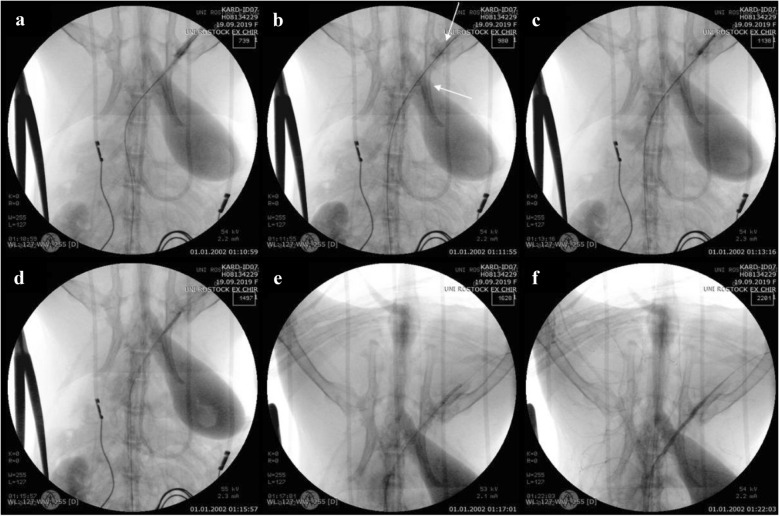

For the second approach to achieving vessel perforation by means of overdilation along with the bursting of a balloon catheter, the explosion of the balloon catheter (Fig. 3a) resulted in a massive artery injury and blood leakage (Fig. 3b). This rupture was fixed by implantation of three covered stent grafts (Fig. 3c–f).

Fig. 3.

Angiography of the iliac artery perforation by overdilation and the bursting of a balloon catheter. a The burst of overdilated balloon catheter. b Leakage of blood out of the ruptured vessel. Implantation of the (c) first, (d) second, and (e) third covered stents. f Verification of the leakage being sealed after stent implantation